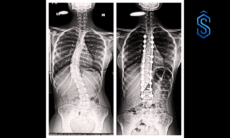

The cancer had affected three ribs, making wide excision and reconstruction essential. The multidisciplinary team at Wockhardt Hospitals, led by Dr Tanveer Majeed (Consultant Surgical Oncologist), supported by Dr Akshay Deshpande (Plastic & Reconstructive Surgeon) and Dr Shilpa Deshmukh (Onco Anaesthesiologist), performed a challenging procedure. The chest wall was reconstructed using proline mesh and a muscle flap from the back.